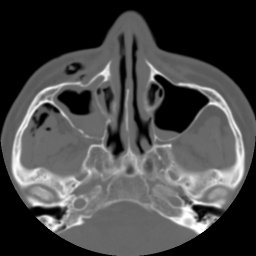

Return to Maxillary Sinus Fracture